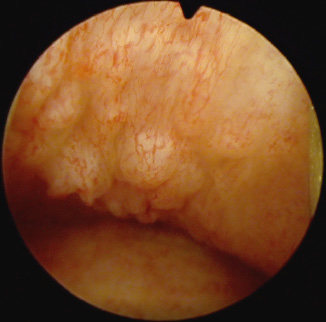

Fig. 3. Vaginoscopy of twin B: solitary small vaginal papillomas.

Because the patient had a twin sister (twin B), the decision was made to perform vaginoscopy and cystoscopy for the second twin (twin B). Her cystoscopy was also normal. On vaginoscopy, solitary small vaginal papillomas were found (Fig. 3). The decision was made not to take a biopsy, and she was not analyzed for HPV DNA.